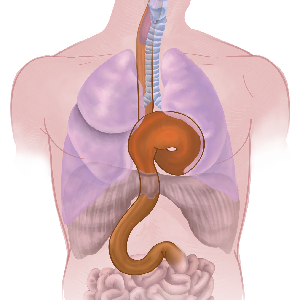

Detailreiche Fotografien aus der medizinischen Praxis ergänzen die Texte; moderne, genaue,

wissenschaftliche Zeichnungen geben Einblick in die Anatomie und die Funktion der Lunge und

anderer Organe.